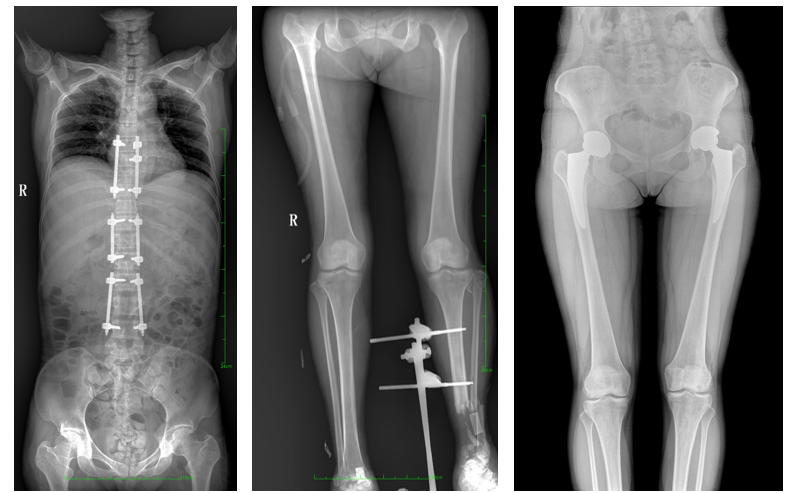

一、成像面積大。17"*34"有效視野,一次成像不拼接。相較于多張攝影再軟件拼接的DR設備,大視野平板動態DR解決了拼接圖像存在密度不均勻,拼接處圖像配準和放大效應等問題,給臨床帶來了大視野影像解決方案,可一次性覆蓋全脊柱或雙下肢影像。

PLX8600大視野平板動態DR可在低輻射劑量下獲得患者站立位、臥位的高質量影像。搭載自主研發的圖像均衡處理系統,能夠很好的均衡人體不同厚度組織的影像,視野大,圖像清晰,層次豐富。